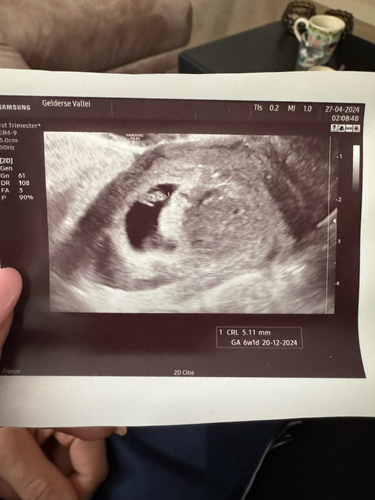

Ik heb zelf ook een hematoom in de baarmoeder. Ik verlies sinds week 5 al bruine afscheiding en nog steeds.Ik heb een keer bloed gehad was niet veel. Verder heb ik geen klachten.

Mijn verloskundige zei dat ik een flinke innesteling gehad zou hebben waardoor de hematoom ontstaan is.